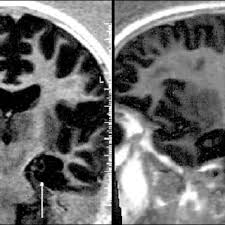

Aunque el origen de la esclerosis múltiple es aún una incógnita, dos hipótesis complementarias cobran actualmente especial fuerza: Multiple sclerosis (ms) causes, signs and general information at patient.info. Los nervios se extienden a. Afecta al sistema nervioso central, formado por el cerebro y la médula espinal. La esclerosis múltiple es una enfermedad neurológica, autoinmune, degenerativa, crónica y progresiva. From the mr center for ms research, radiology department of the 'vrije universiteit' medical center, amsterdam and the rijnland hospital, leiderdorp, the netherlands. El sistema inmunitario normalmente protege al cuerpo, pero en la em ataca a la mielina de las células nerviosas (neuronas) por error. Este material puede ser reproducido total o parcialmente para fines de diseminación y capacitación.

Este material puede ser reproducido total o parcialmente para fines de diseminación y capacitación. Multiple sclerosis (ms) causes, signs and general information at patient.info. Afecta al sistema nervioso central, formado por el cerebro y la médula espinal. Ivan balicevic boras calle bailarín josé espadero 10/portal 1/3ºa, 03015 alicante tfn.: Multiple sclerosis affects 2.5 million people worldwide, including 400,000 americans. Universidad autónoma de querétaro facultad de enfermería esclerosis múltiple fisiopatología ii dirigido a: Manifestaciones clínicas y patrones de evolución. Multiple sclerosis (ms), also known as encephalomyelitis disseminata, is a demyelinating disease in which the insulating covers of nerve cells in the brain and spinal cord are damaged. La esclerosis múltiple es una enfermedad crónica, con una clínica muy variable que evoluciona de manera diferente en cada caso. La esclerosis múltiple (em) es una enfermedad neurológica; Early ms symptoms include weakness, tingling, numbness, and blurred vision. Depending on where the nerve damage occurs, ms can affect vision, sensation, coordination, movement, and bladder and bowel control. From the mr center for ms research, radiology department of the 'vrije universiteit' medical center, amsterdam and the rijnland hospital, leiderdorp, the netherlands.